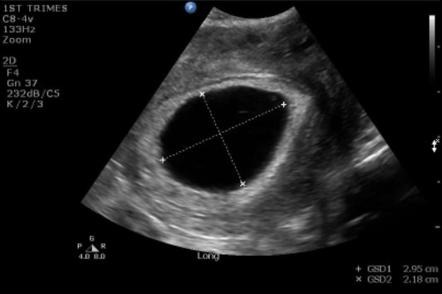

Kesede Bebek Görülmemesi

Kesede Bebek Görülmemesi.

gebelikte kesenin olup bebegin olmamasi hafta hafta gebelik hamilelik takibi bebek gelisimi